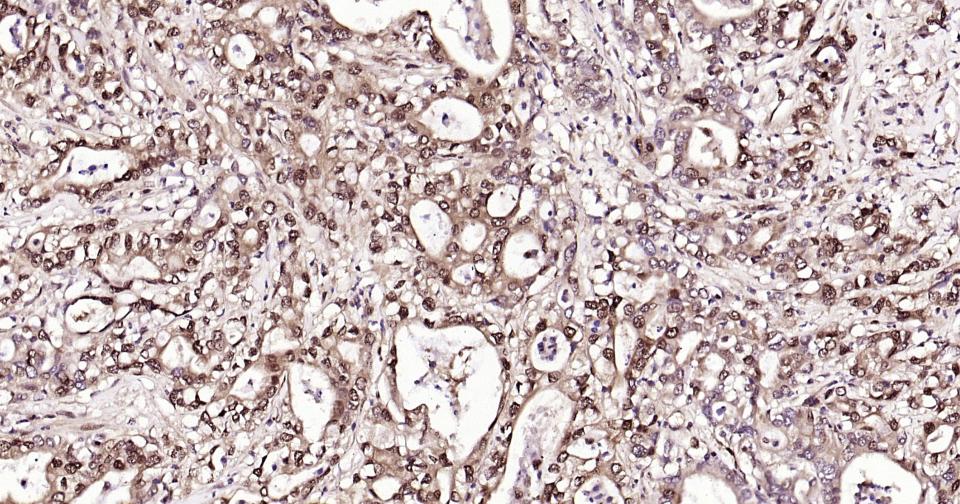

Paraformaldehyde-fixed, paraffin embedded Human Colon; Antigen retrieval by boiling in sodium citrate buffer (pH6.0) for 15 min; Antibody incubation with K48-linkage specific ubiquitin? Monoclonal Antibody, Unconjugated(bsm-63005R) at 1:200 overnight at 4°C, followed by conjugation to the bs-0295G-HRP and DAB (C-0010) staining and DAB (C-0010) staining.

Paraformaldehyde-fixed, paraffin embedded Human Pancreatic Cancer; Antigen retrieval by boiling in sodium citrate buffer (pH6.0) for 15 min; Antibody incubation with K48-linkage specific ubiquitin? Monoclonal Antibody, Unconjugated(bsm-63005R) at 1:200 overnight at 4°C, followed by conjugation to the bs-0295G-HRP and DAB (C-0010) staining and DAB (C-0010) staining.